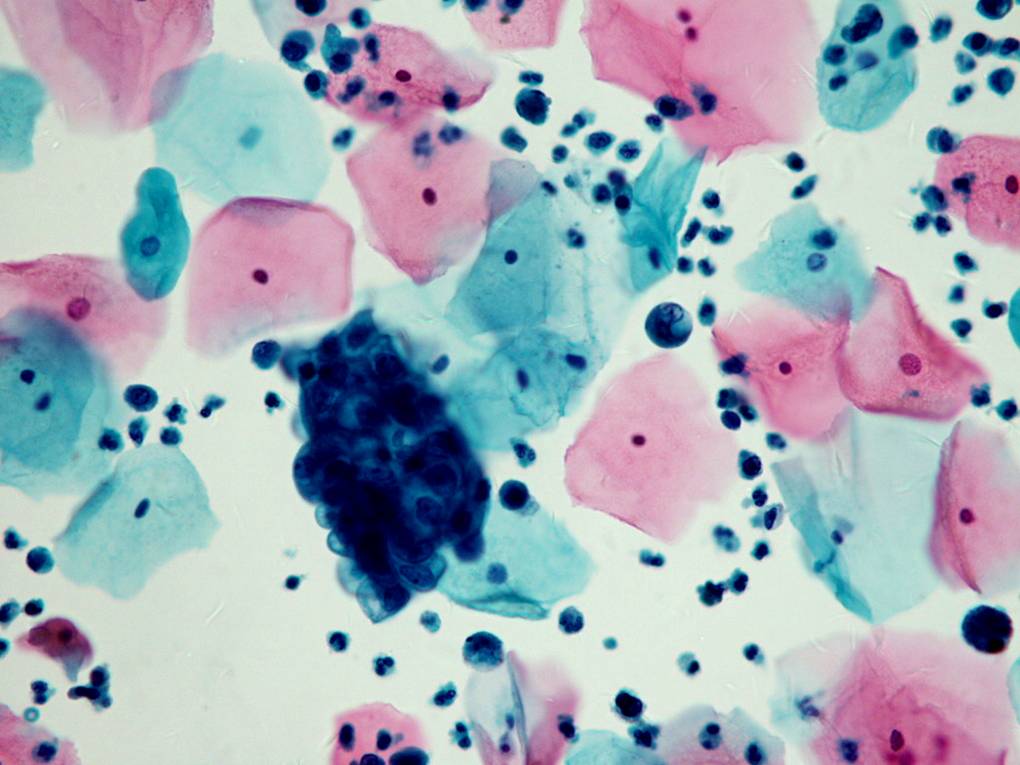

TBS-90.子宫内膜腺癌

TBS-91.子宫内膜腺癌

TBS-92.子宫外腺癌(结肠癌转移)

TBS-93.子宫外腺癌(乳腺癌)

TBS-94.其他恶性肿瘤:转移性移形细胞癌